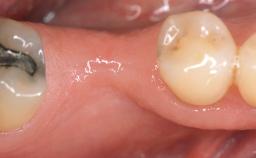

Implant Placement in the Esthetic Zone and Coverage of Multiple Gingival Recessions

This case illustrates use of a modified ‘tunnel’ technique, which has been shown to be highly effective in root coverage procedures. The tunnel technique is used to achieve soft-tissue augmentation across the anterior area, including the planned implant site, using collagen matrix as grafting material. The patient is a 47-year-old woman with high esthetic expectations. Her main concern was the appearance of the anterior teeth and their “elongation”.

Case Type Single-Tooth Space

# of Teeth 1

# of Implants 1